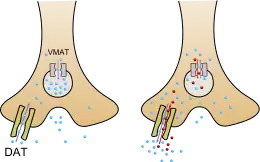

Methamphetamine has been identified as a potent full agonist of trace amine-associated receptor 1 (TAAR1), a G protein-coupled receptor (GPCR) that regulates brain catecholamine systems.[116][117] Activation of TAAR1 increases cyclic adenosine monophosphate (cAMP) production and either completely inhibits or reverses the transport direction of the dopamine transporter (DAT), norepinephrine transporter (NET), and serotonin transporter (SERT).[116][118] When methamphetamine binds to TAAR1, it triggers transporter phosphorylation via protein kinase A (PKA) and protein kinase C (PKC) signaling, ultimately resulting in the internalization or reverse function of monoamine transporters.[116][119] Methamphetamine is also known to increase intracellular calcium, an effect which is associated with DAT phosphorylation through a Ca2+/calmodulin-dependent protein kinase (CAMK)-dependent signaling pathway, in turn producing dopamine efflux.[120][121][122] TAAR1 has been shown to reduce the firing rate of neurons through direct activation of G protein-coupled inwardly-rectifying potassium channels.[123][124][125] TAAR1 activation by methamphetamine in astrocytes appears to negatively modulate the membrane expression and function of EAAT2, a type of glutamate transporter.[57]

In addition to its effect on the plasma membrane monoamine transporters, methamphetamine inhibits synaptic vesicle function by inhibiting VMAT2, which prevents monoamine uptake into the vesicles and promotes their release.[126] This results in the outflow of monoamines from synaptic vesicles into the cytosol (intracellular fluid) of the presynaptic neuron, and their subsequent release into the synaptic cleft by the phosphorylated transporters.[127] Other transporters that methamphetamine is known to inhibit are SLC22A3 and SLC22A5.[126] SLC22A3 is an extraneuronal monoamine transporter that is present in astrocytes, and SLC22A5 is a high-affinity carnitine transporter.[117][128]